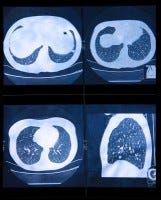

The National Lung Screening Trial showed that 3 annual low-dose chest CT scans in people with heavy smoking histories (30+ pack-years) saved lives, reducing the risk of death from lung cancer by a relative 20% compared to screening with annual chest X-rays. With 160,000 lung cancer deaths in the U.S. each year, widespread CT screening could theoretically prevent 12,000 lung cancer deaths each year.

Skeptics pointed out that the absolute risk reduction in lung cancer death seen in NLST was rather low, requiring 320 people to be screened with CT in order to prevent one death from lung cancer. Along the way, more than one-third of the ~27,000 screened had false positive CT scans, with associated health care expenses, anxiety, and avoidable biopsies. Widespread lung cancer CT screening of the 9 million U.S. adults meeting NLST criteria has been estimated to cost $1.5 billion / year and about $240,000 per life saved. The leading expert bodies in pulmonary medicine cautiously endorsed lung cancer screening, but only for people meeting entry criteria for the NLST (age 55-74, 30+ pack-years, quit < 15 years ago).